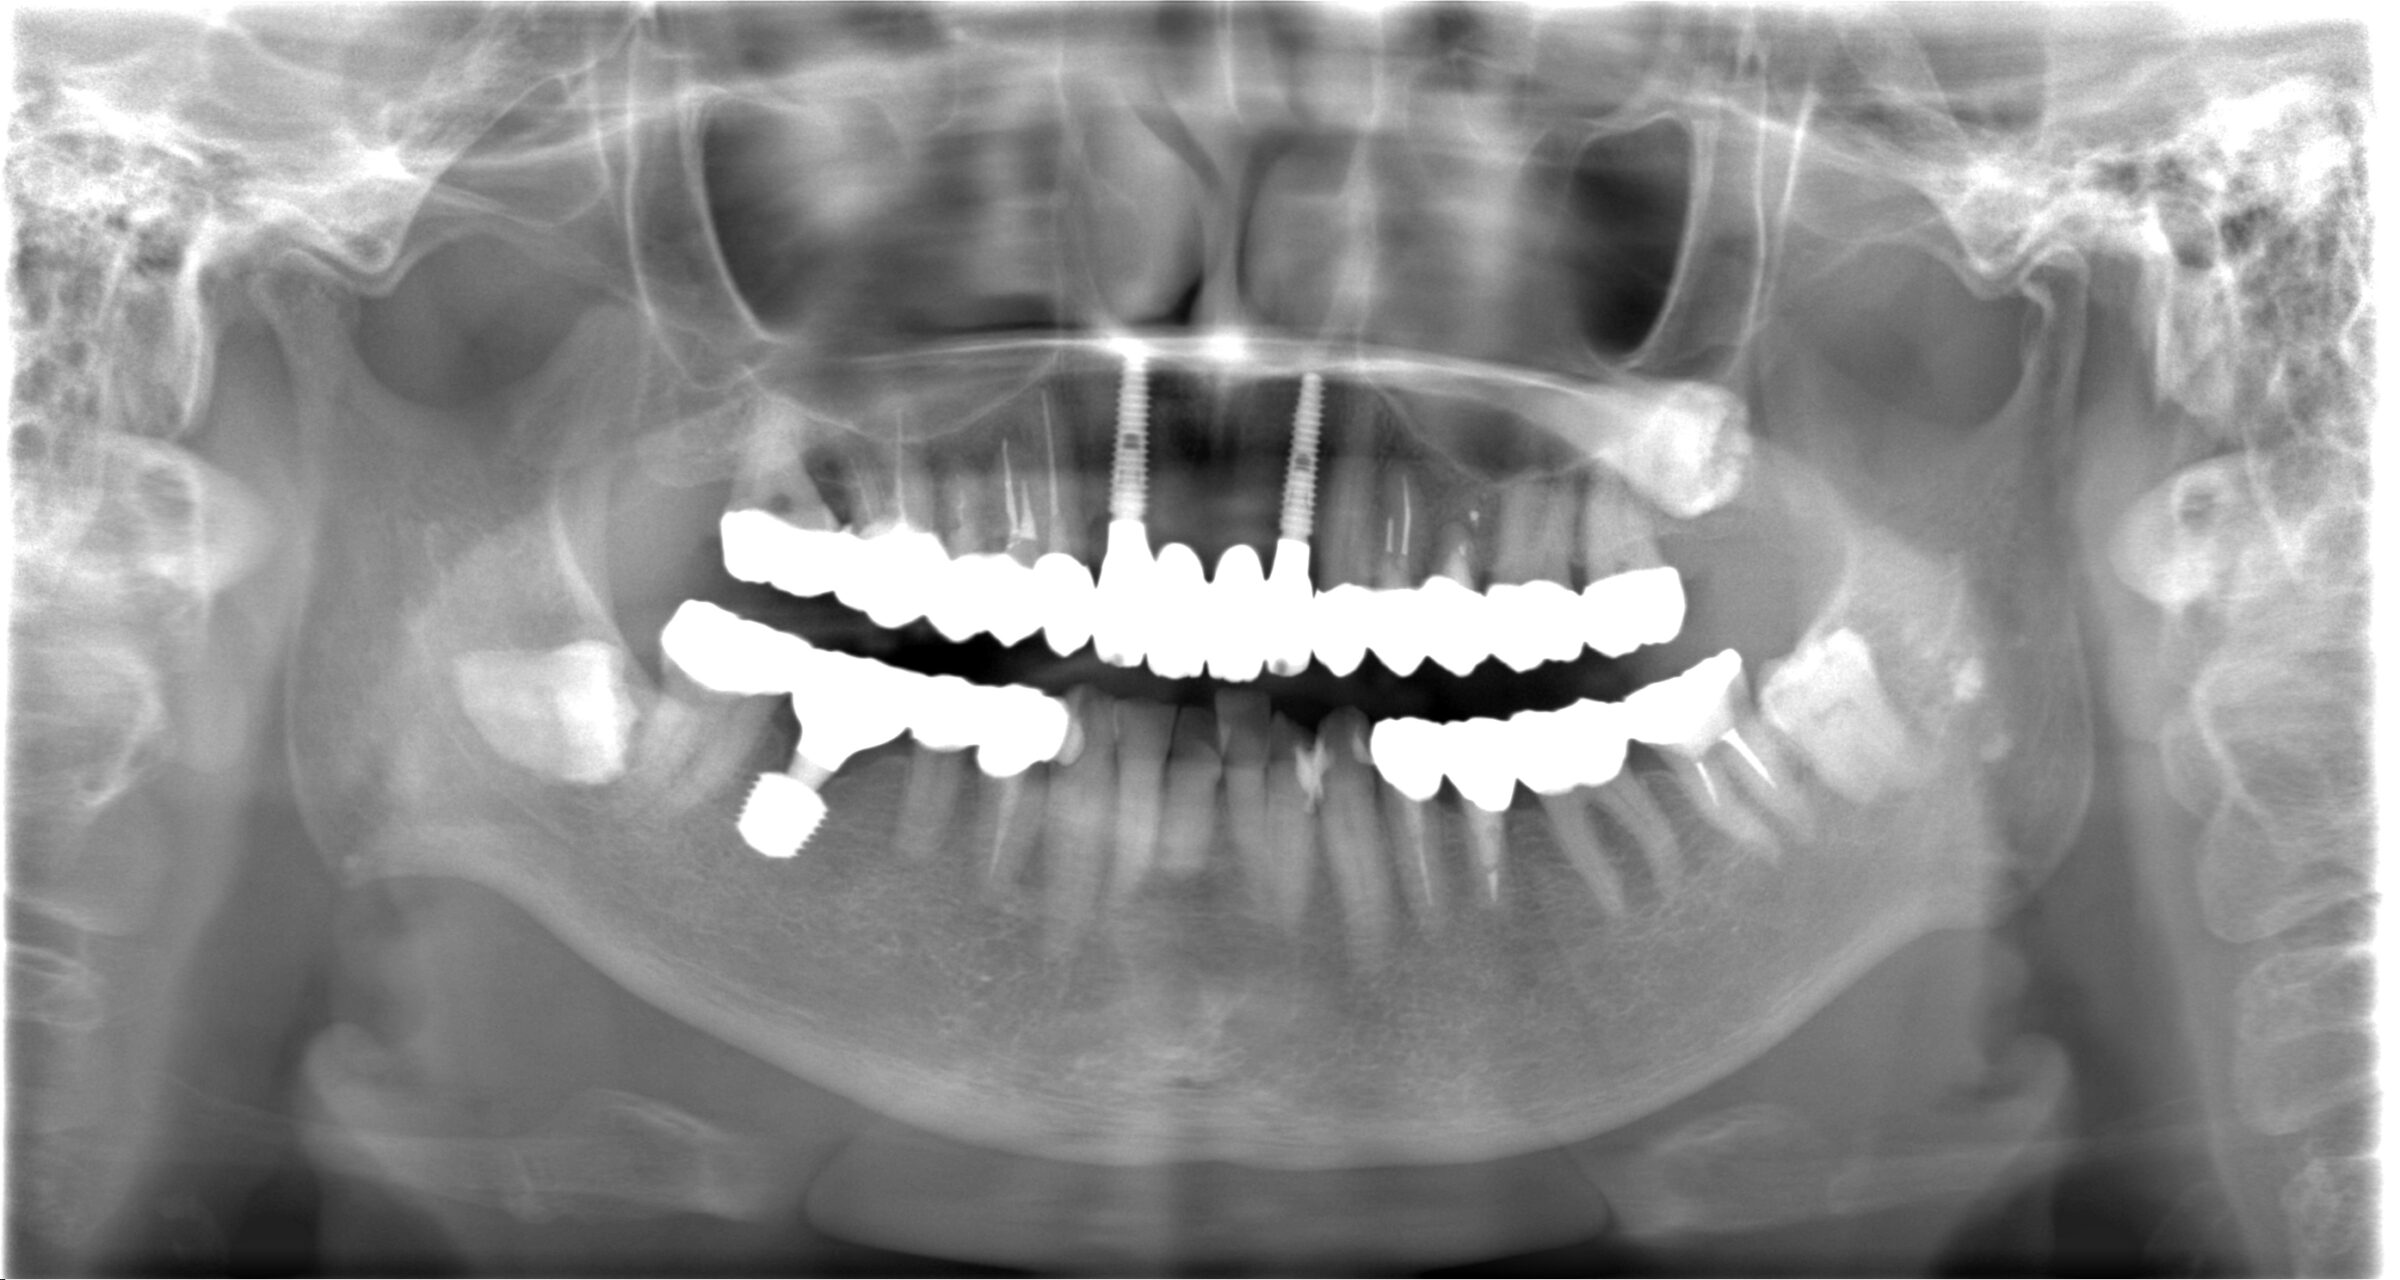

治療後のレントゲン写真

前歯プレミアムインプラント2本→1本あたり495,000円(税込)

前歯プレミアムセラミックダミー2本→1本あたり165,000円(税込)